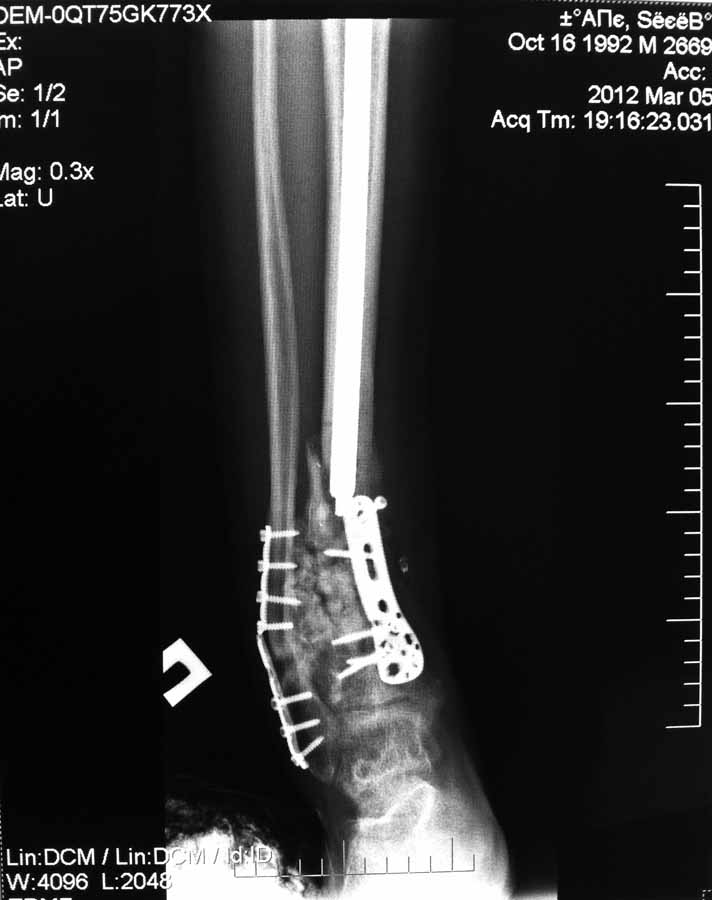

[Ortho] Несращение дистального отдела костей голени

Вчера не вышло выслать все фото. Последние снимки более более драматичные, как раз с куском проксимального стержня и пластиной что не к месту!

Вложение не в текстовом формате было извлечено…

Имя     : IMG_0326.JPG

Тип     : image/jpg

Размер  : 46072 байтов

Url     : http://weborto.net:8080/pipermail/ortho/attachments/20120504/3cea5761/attachment-0003.jpg